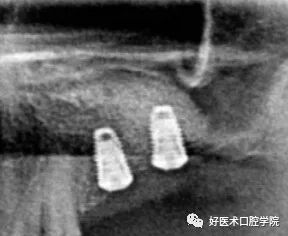

常见上颌窦底部,局部黏膜充血外渗膨胀,由于液体潴留在结缔组织而产生,呈微小的半球形或椭圆形,均匀而且不透明,CBCT和根尖周片显现明显,表现为上颌窦底的穹窿形,未被上皮包绕固称为假性囊肿,多被认为是牙源性感染导致,多可见因牙周病或根尖周病破坏的牙槽骨。